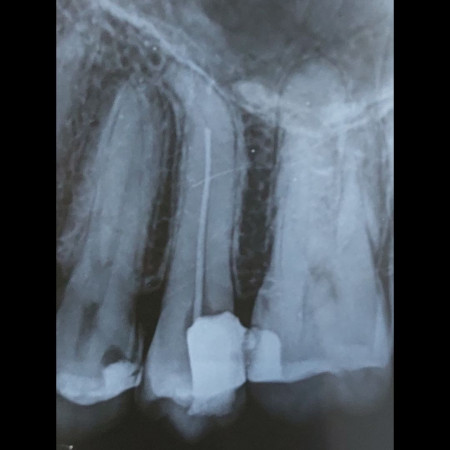

One Visit Root Canal Treatment

When a tooth is infected or the pulp is exposed due to dental trauma, it can be saved by doing a root canal treatment, commonly known as a Nerve filling. 95% of our root canal treatments are completed in one visit, which in turn saves your time and reduces radiation exposure too. We take pride in delivering root canal treatments with minimum post-operative pain and only a very few patients require post-operative use of Antibiotics.

Advanced Complex Root Canal Treatments And Re-treatments

Not all root canal treatments are straightforward. The shape and degree of formation of the root of some teeth require expert intervention. We are proud to house some of the best-trained specialists at Danthaja to handle such cases. Furthermore, failed root canal treated cases done elsewhere, which need re-treatment will also be handled by our specialists.